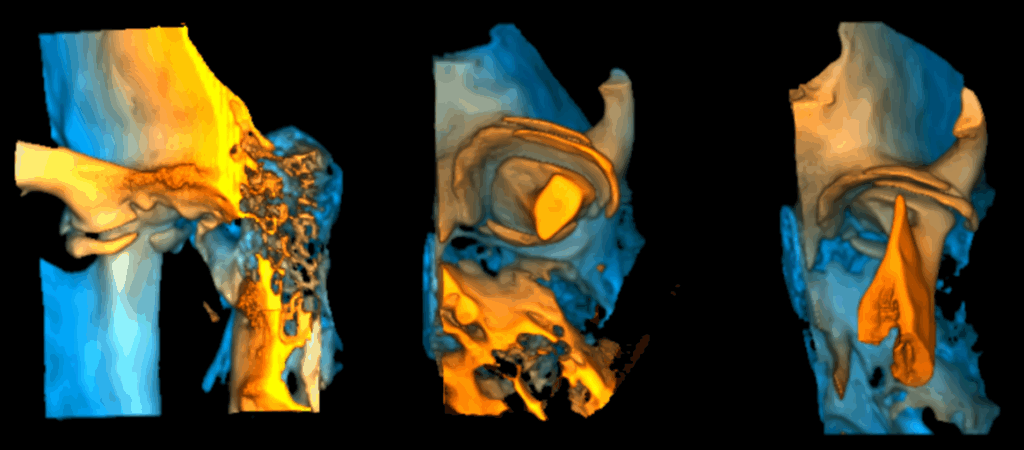

En la ampliación imagenológica con tomografía computarizada de haz cónico se identifica en el lado derecho se aprecia aplanamiento y esclerosis de la cabeza condilar, con formación de osteofito, presencia de pseudoquiste subcondral y erosión en el contorno superior, además de una disminución del espacio articular en las regiones posterior y lateral. En el lado izquierdo se observa aplanamiento y esclerosis que comprometen la cabeza y el cuello condilar, con osteofito asociado y múltiples cuerpos óseos libres alrededor del cóndilo. Asimismo, se identifica una reducción del espacio articular en las regiones posterior, superior, medial y lateral.

RECONSTRUCCIÓN 3D